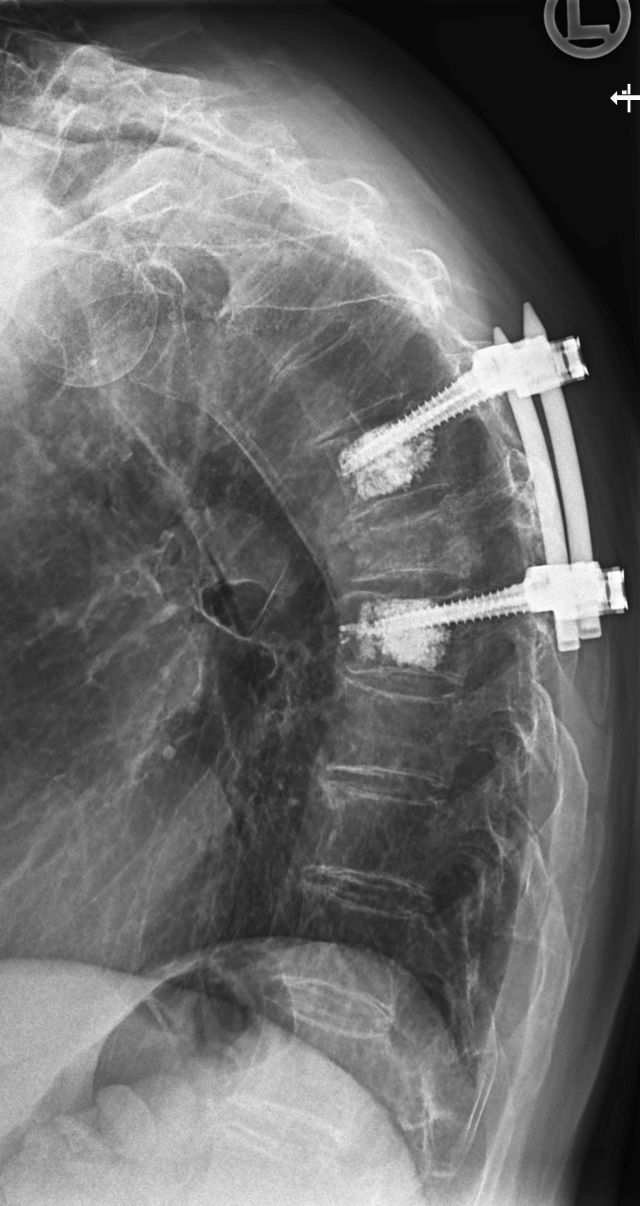

ist eine Skeletterkrankung mit Verminderung bzw. Verlust der Knochensubstanz, die zum Auftreten von Knochenbrüchen führen kann. Besonders häufig tritt die Krankheit im fortgeschrittenen Lebensalter auf. Sichtbare Zeichen einer Osteoporose können sein: Größenabnahme von mehr als 4 cm und/oder Entwicklung eines Rundrückens. Überdurchschnittlich häufig betroffen von einer Osteoporose sind Frauen nach der letzten Menstruation (Menopause).

Die Knochendichtemessung erfolgt meist mit einem speziellen Röntgengerät, das die Menge an Mineralstoffen in den Knochen misst. Die Messung wird in der Regel an der Wirbelsäule und dem Oberschenkelhals durchgeführt.

Die Messung der Knochendichte (Osteodensitometrie) ist die einzige Möglichkeit zur Früherkennung der Osteoporose, d.h. vor dem Auftreten von Frakturen. Ist es bereits zu Frakturen gekommen, wird die Knochendichtemessung zur Sicherung der Diagnose einer Osteoporose und zur Beurteilung des Osteoporose-Grades verwendet.

Die Knochendichtemessung mittels CT ist eine genaue Methode, aber mit einer höheren Strahlenbelastung verbunden und daher nicht für die Routineanwendung geeignet. Die DXA-Messung erfolgt an der Hüfte und der Lendenwirbelsäule. Knochendichtemessungen von anderen Körperregionen, wie zum Beispiel dem Handgelenk oder der Ferse, sind weniger genau.